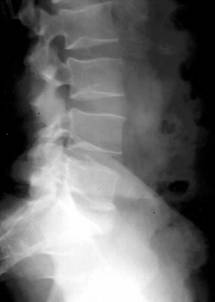

D. Leziuni degenerative ale coloanei vertebrale